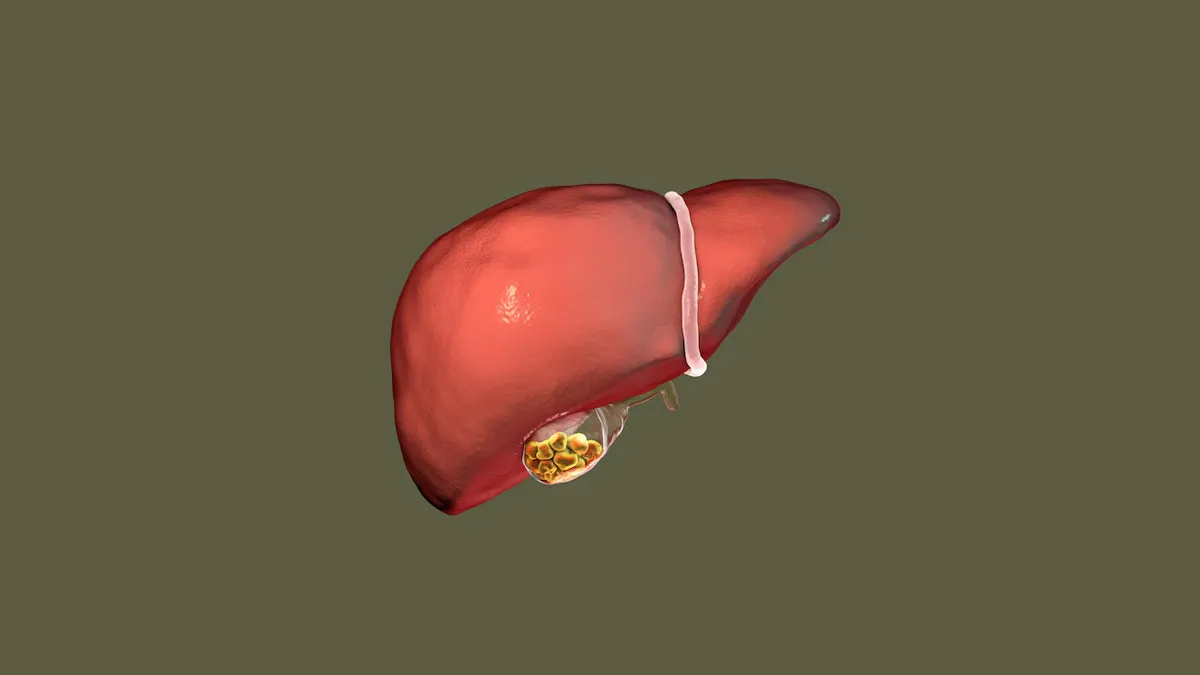

पित्त की पथरी यानी गॉल ब्लैडर स्टोन आज के समय में एक आम लेकिन बेहद परेशान करने वाली स्वास्थ्य समस्या बन चुकी है। यह पथरी गॉल ब्लैडर में कोलेस्ट्रॉल बिलीरुबिन के जमने से बनती है और समय के साथ यह दर्द, अपच, मतली, सूजन और यहां तक कि इमरजेंसी सर्जरी का कारण बन सकती है।

गॉल ब्लैडर का काम पित्त को जमा करना और पाचन के लिए उसे छोटी आंत में छोड़ना है। इससे हमारा खाना पचता है, लेकिन जब पित्ताशय ही ठीक ढंग से काम न करे तो मुश्किल पैदा हो सकती है।

Image Credit: freepik